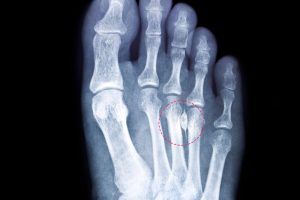

This is a painful condition that affects the ball of the foot. This ball is typically between the third and fourth toes. If you look at images of Morton’s neuroma in Phoenix, you can see it occurs when the tissue around the nerves leading to your toes thickens. This thickening causes sharp, burning pain in the ball of your foot. This condition especially happens with high-heeled shoes and repetitive stress.

- We use X-rays or ultrasounds to rule out other conditions and confirm the diagnosis.